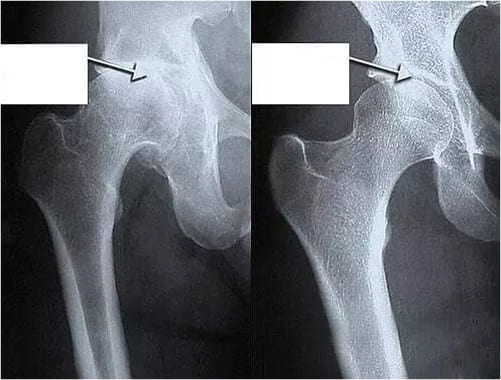

Вы только посмотрите на рентген суставов до и после использования «Сусталита»:

Женщина. 54 года. Ее сустав полностью восстановился.

Продолжительность курса: 2,5 месяца.

Изменения в суставе бедра у 44-летнего мужчины.

Острые боли, которые его мучили в течение 2-х лет, исчезли.